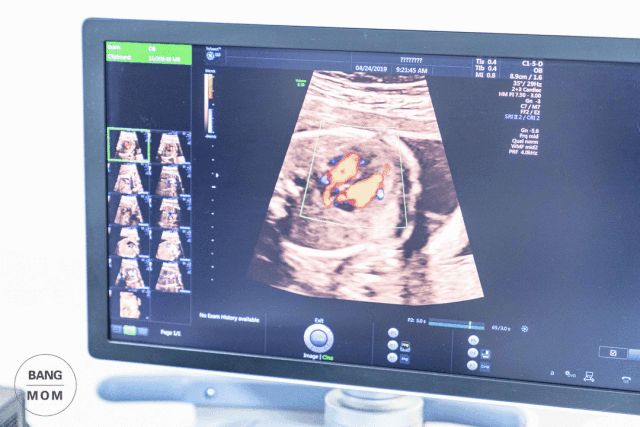

做四维彩超的时候,医生的屏幕上,会显现出胎儿在母亲体内的实时动态活动影像。吕主任经常会捕捉到胎儿可爱的小动作和小表情,有的宝宝会吐舌头、歪嘴笑、打哈欠,还能逮到TA们撒尿、做体操、甚至是双胞胎打架……

36年的从医经历,从一维的回波、到二维的直观成像、到计算机重构的三维图像、再到实时动态的四维彩超,吕主任以精益求精的医学追求和严谨的行医态度,为临床提供准确而快捷的检查报告、践行着“胎儿健康把关人”的职责。

产科超声的一个最重要的作用就是排查胎儿是否有畸形,中国每年有80-120万的畸形胎儿出生,占总人口的4%-6%,因此卫生部《产前诊断技术管理条例》规定,在18-24周的超声检查中,需要筛查6项致命的胎儿畸形,包括无脑儿、严重脑膨出、严重开放性脊柱裂、严重腹壁缺损及内脏外翻、单腔心、致命性软骨发育不良。